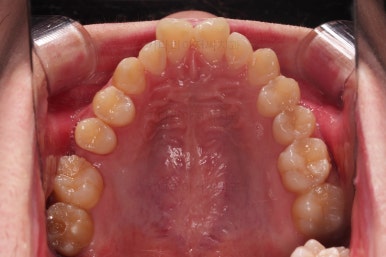

부산교정치과 초진 시 입안의 모습입니다.

앞니가 삐뚤어서 결손치아가 없었더라도 교정치료를 원하셨던 상황이었고요.

오른쪽 어금니 맞물림은 결손치아도 그렇지만 전반적인 앞뒤 차이가 있는 부정교합이 있었어요.